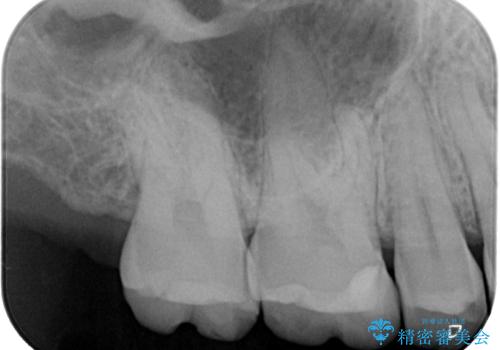

- 保険診療で治療した銀歯のやり替え希望の患者様です。

銀歯とその下の虫歯を除去し、形を整え、精度の良いシリコーンによる型どりを行いました。

セラミックインレーを接着する際は、ラバーダム防湿を行いました。